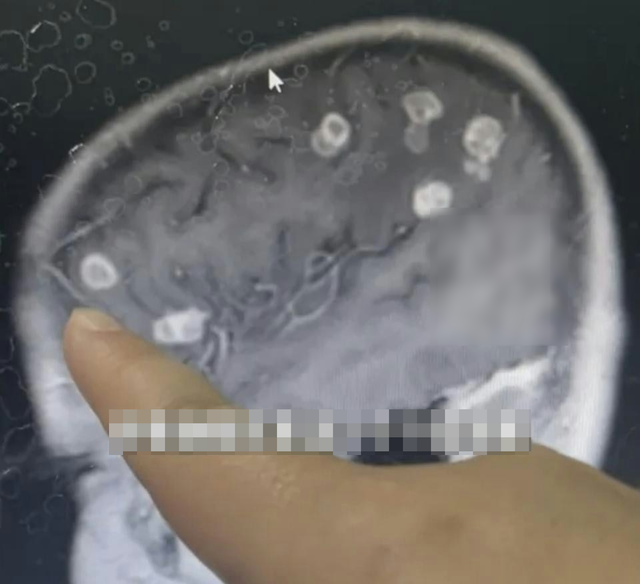

Tại Trung Quốc, một bé gái 6 tuổi sau khi phụ giúp dọn dẹp nhà cũ đã sốt cao liên tục suốt 17 ngày. Khi được đưa đi bệnh viện, bác sĩ phát hiện não của bé xuất hiện hơn 20 ổ tổn thương, suýt dẫn đến hoại tử não và rơi vào trạng thái sống thực vật. Nguyên nhân đến từ việc bé đã hít phải lượng lớn bụi mốc phát sinh từ đồ đạc ẩm mốc lâu ngày. Các xét nghiệm cho thấy não bộ của bé bị nhiễm nấm Aspergillus fumigatus, hay còn gọi là nấm khói. Bác sĩ cảnh báo, nếu không được can thiệp kịp thời, loại nấm này có thể xâm nhập não, gây hoại tử mô và để lại di chứng cực kỳ nặng nề.

Aspergillus fumigatus là chủng nấm có độc lực mạnh nhất trong họ nấm Aspergillus. Chúng thường tồn tại trong ngũ cốc, đất và đặc biệt phát triển mạnh ở môi trường ẩm, nhiệt độ từ 37 đến 45 độ C, rất phổ biến trong nhà cũ, góc tường, trần nhà, thảm lâu ngày không vệ sinh. Bào tử của loại nấm này cực nhỏ, chỉ từ 2 đến 10 micromet, dễ dàng theo không khí đi vào đường hô hấp.